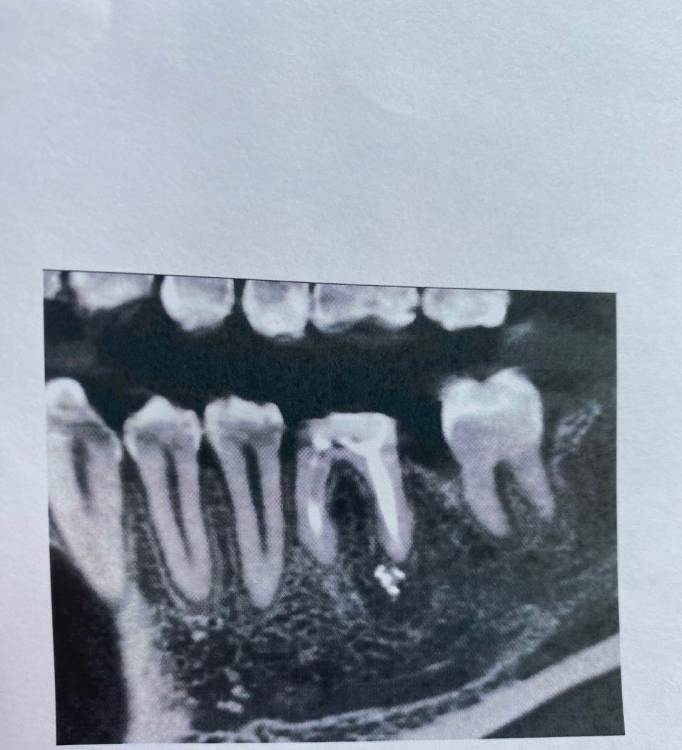

K3000 Опубликовано 24 марта, 2022 Поделиться Опубликовано 24 марта, 2022 Здравствуйте всем! Хотела узнать у специалистов какие варианты у меня есть с моим зубом. Это многострадальная нижняя 6ка, разрушена на уровне десны уже лет как 10, в зуб был поставлен штифт и был покрыт коронкой, но коронка слетела( простояв около 3х лет). 2 года ходила в брикетах и верхний зуб антагонист был немного поднят( чтоб освободить место) . Сейчас вопрос , что делать с 6ой , удалять и ставить имплант или пытаться перелечить зуб( сказали что корень хороший , но сильно разрушен зуб, надо вытаскивать штифт, что опасно и можно сломать корень зуба). Снимки зуба прилагаю. https://imgur.com/a/XaGq50M Ссылка на комментарий

Irouil Опубликовано 24 марта, 2022 Поделиться Опубликовано 24 марта, 2022 Условия для имплантации близки к оптимальным, условия для сохранения зуба близки к неподходящим Я бы исходил из мнения протезиста, в моей практике в 99% случаев такие зубы ортопеды отправляют на удаление 1 1 Ссылка на комментарий